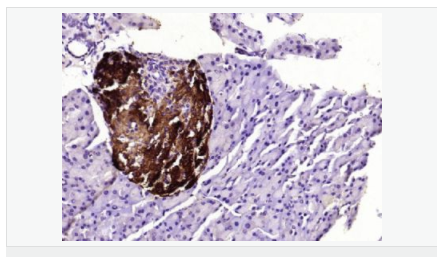

| 产品应用 | WB=1:500-2000 ELISA=1:5000-10000 IHC-P=1:100-500 IHC-F=1:100-500 ICC=1:100-500 IF=1:100-500 (石蜡切片需做抗原修复) not yet tested in other applications. optimal dilutions/concentrations should be determined by the end user. |